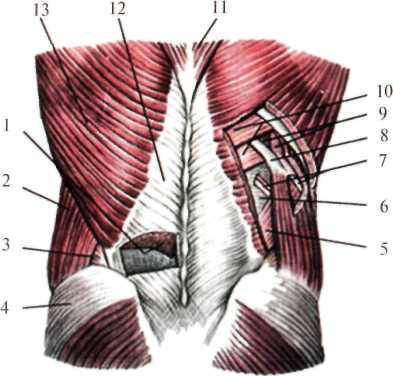

Послойное расположение слоев латерального отдела поясничной области вначале такое же, как и в медиальном отделе: кожа, подкожная клетчатка, поверхностная фасция, пояснично-ягодичная жировая подушка и собственная фасция спины, за ней располагается широчайшая мышца (m. latissimus dorsi) (рис.2.2). Эта мышца берет начало от остистых отростков 5-6 нижних грудных позвонков и ребер, поверхностного листка пояснично-грудной фасции, а также гребня подвздошной кости. Волокна мышцы направляются кверху и латерально и прикрепляются к гребню малого бугорка плечевой кости (crista tuberculi minoris humeri). В этом же слое лежит наружная косая мышца живота (m. obliquus externus abdominis), волокна которой идут сверху вниз, сзади наперед.

В следующем слое залегают: вверху – нижняя задняя зубчатая мышца (m. serratus posterior nferior), внизу – внутренняя косая мышца живота (m. obliquus internus abdominis). Волокна их направляются снизу вверх и сзади наперед. Под зубчатой и внутренней косой мышцами живота располагается поперечная мышца (m. transversus abdominis). Следующим слоем является поперечная фасция (fascia transversa, seu fascia endoabdominalis), а затем забрюшинное пространство.

В латеральных отделах поясничной области имеются дефекты, один из них напоминает форму треугольника – поясничный треугольник Пти (trigonum lumbale seu Petiti) (рис.2.2), ограниченный наружным краем широчайшей мышцы спины, внутренним краем наружной косой мышцы живота и снизу – гребнем подвздошной кости. Дном треугольника служит внутренняя косая мышца живота.

Вторым дефектом является пояснично-сухожильное пространство, по форме напоминающей ромб, так называемый ромб Грюнфельда-Лесгафта (spatium tendineum lumbales, rombus lumbalis) (рис.2.2). Он ограничен сверху XII ребром и нижним краем нижней задней зубчатой мышцы, медиально – наружным краем мышцы, выпрямляющей позвоночник, латерально и снизу – внутренней косой мышцей живота. Снаружи дефект прикрыт широчайшей мышцей спины, дном его служит апоневроз поперечной мышцы живота.

В местах описанных дефектов могут образовываться поясничные грыжи, а по ходу межреберных сосудов и нервов возможны выхождения абсцессов и флегмон забрюшинной клетчатки в межмышечную и даже подкожную клетчатку поясничной области.

Рис. 2.2. Мышечные слои поясничной области.

1 – m. erector spinae; 2 – m. obliquus externus abdominis; 3 – trigonum lumbale; 4 – m. gluteus medius; 5 – m. obliquus internus abdominis; 6 – aponeurosis m. transverses abdominis (дно rombus lumbalis);

7 – а.,n. intercostalis; 8 –XII ребро; 9 – mm. intercostales; 10 – m. serratus posterior inferior;

11 – m.trapezius; 12 – fascia thoracolumbalis; 13 – m. latissimus dorsi.